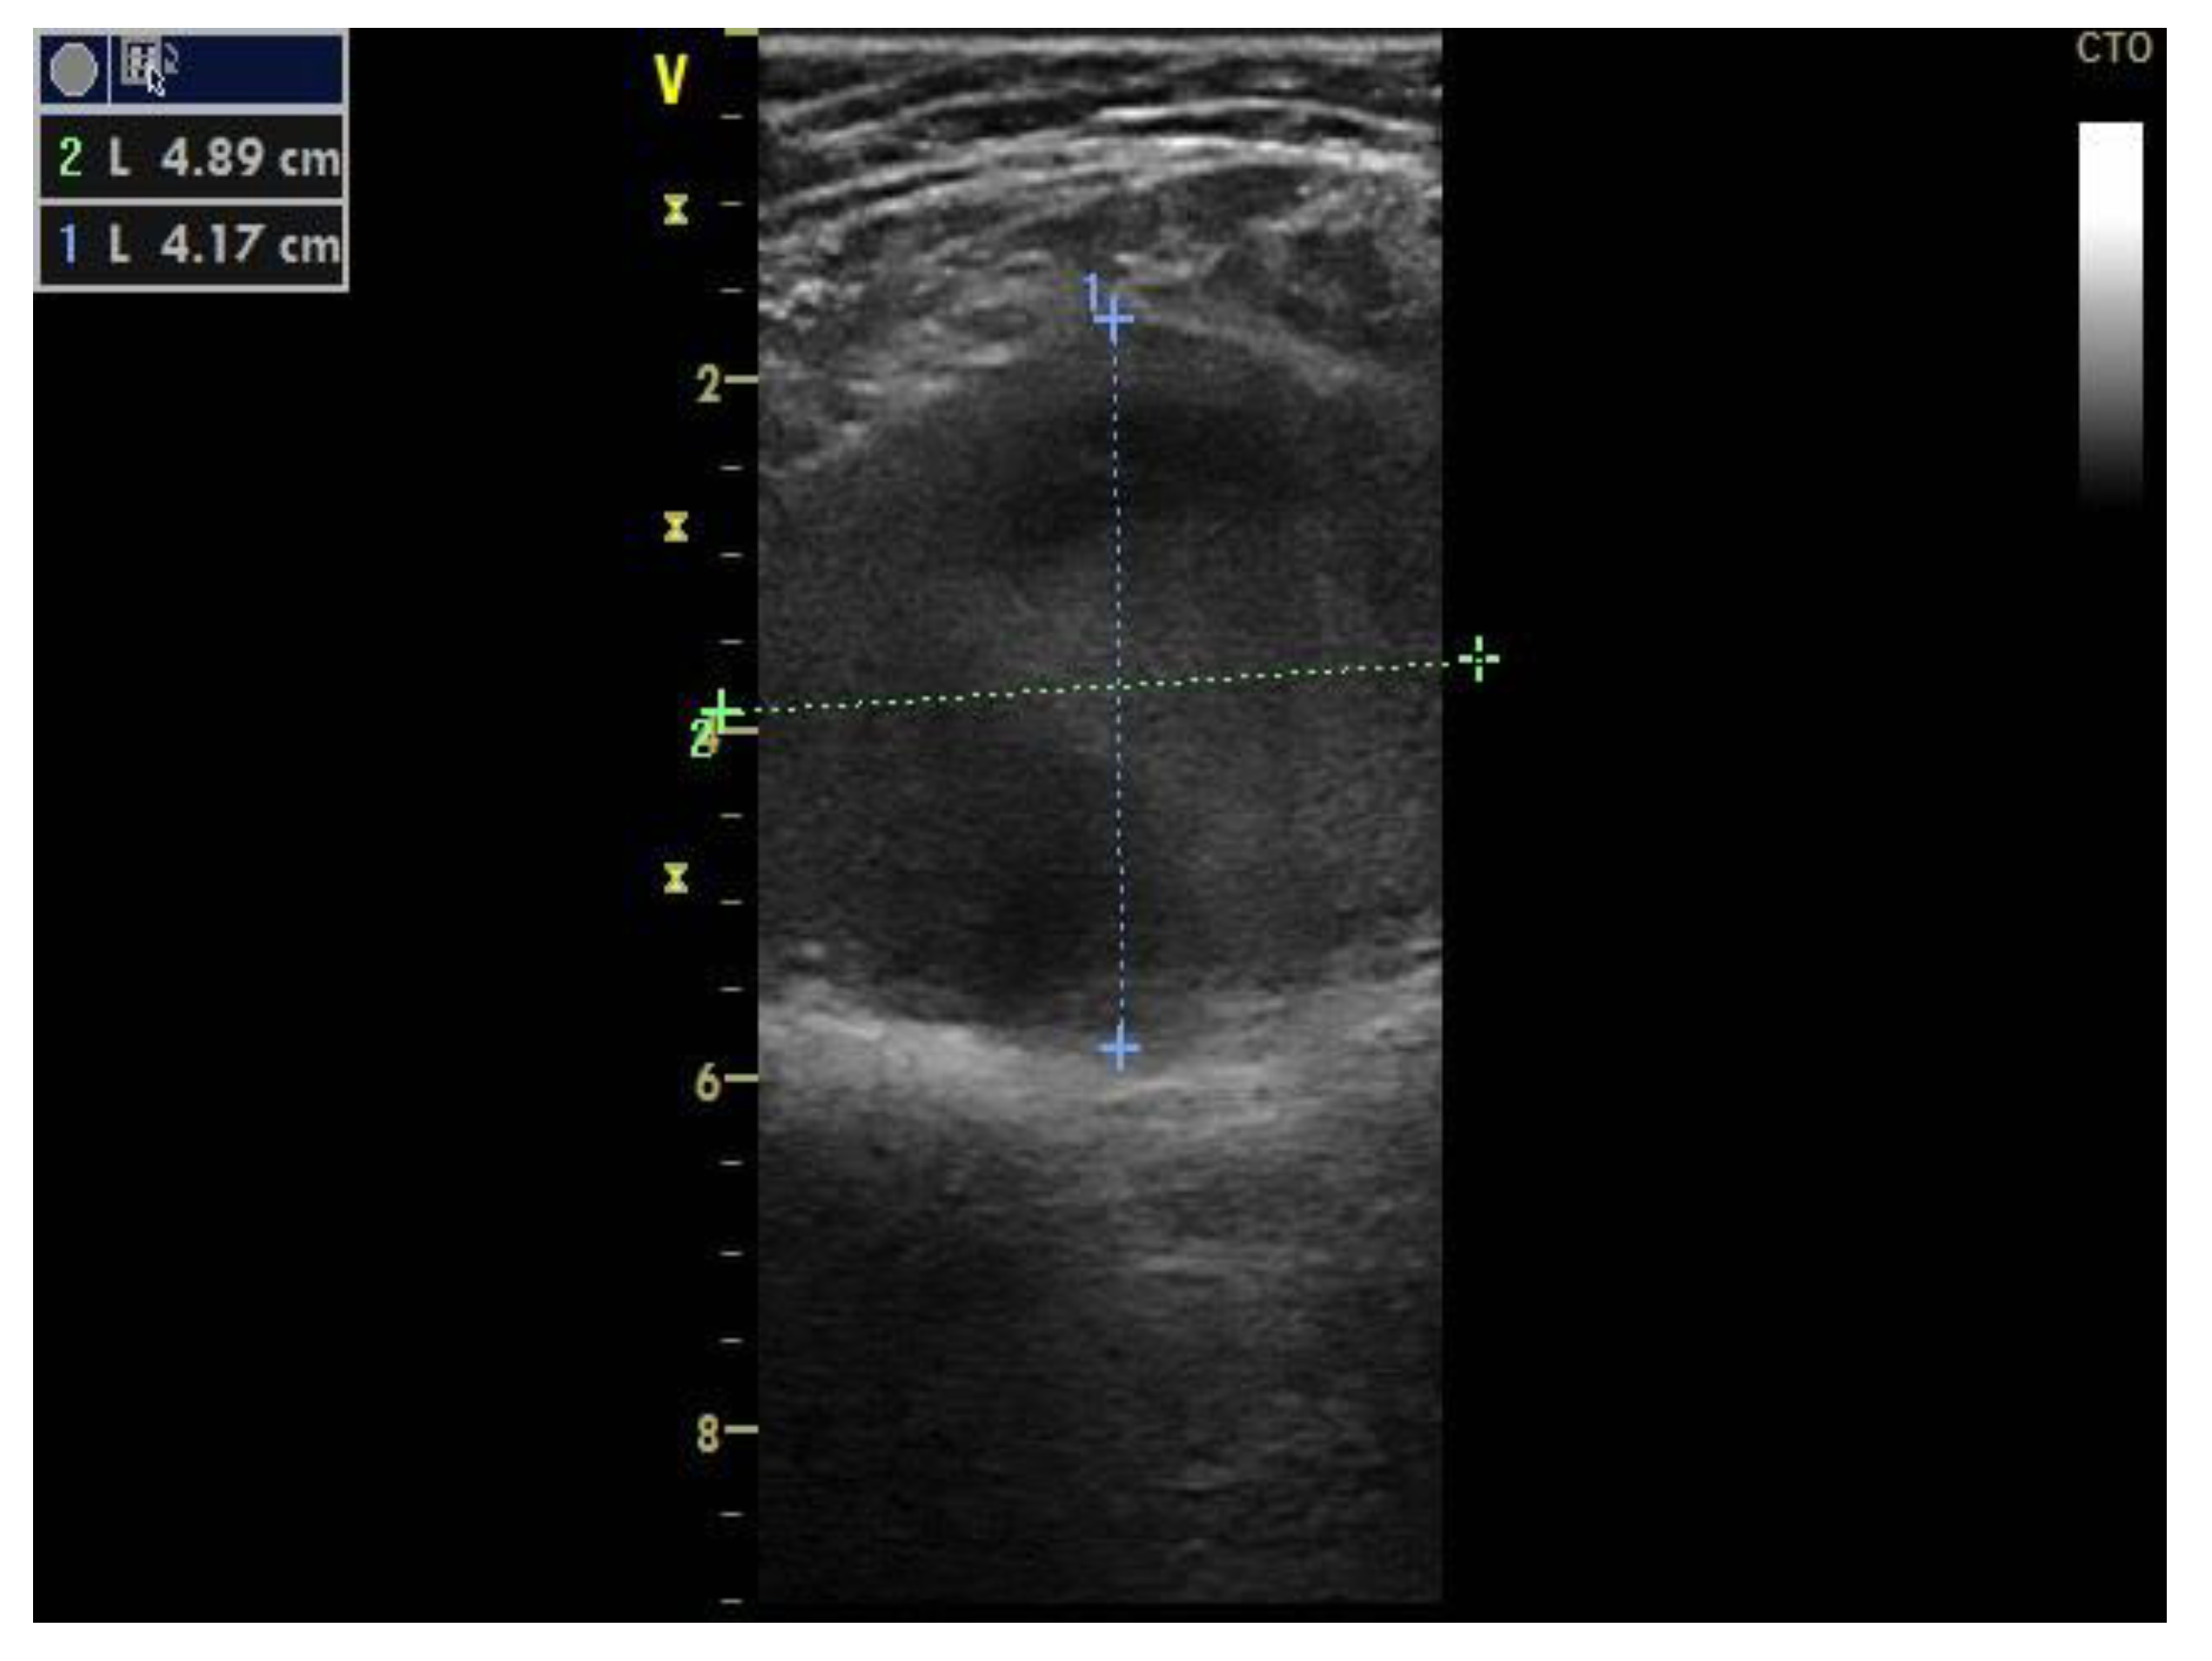

Two-point compression ultrasonography showed no signs of deep vein thrombosis. However, a complete ultrasonography of the lower extremity venous system in real-time B-mode revealed a 6 × 5 × 4 cm anechoic mass located in the cranial extremity of the left popliteal fossa, contiguous to the popliteal vein, with sluggish, swirling blood flow, but no signs of thrombosis (Figure 1).

Figure 1.

Proximal left popliteal vein transverse axis view demonstrates a simple saccular dilatation, with partial thrombosis. The dotted lines represent the PVA’s dimensions.

Doppler spectral analysis revealed low velocity blood flow with normal phasic variation corresponding to a venous waveform.